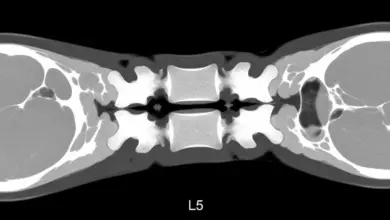

Exames que confirmam

O caminho começa com história clínica e exame físico detalhados. Em seguida, os exames de imagem definem o grau e estabilidade.

- Radiografias AP e perfil, com medidas de Meyerding e dos ângulos.

- Radiografias dinâmicas em flexão e extensão, para avaliar a instabilidade.

- Ressonância magnética, para observar o disco, facetas, canal e raízes.

- Tomografia, útil em dúvidas anatômicas e planejamento cirúrgico.